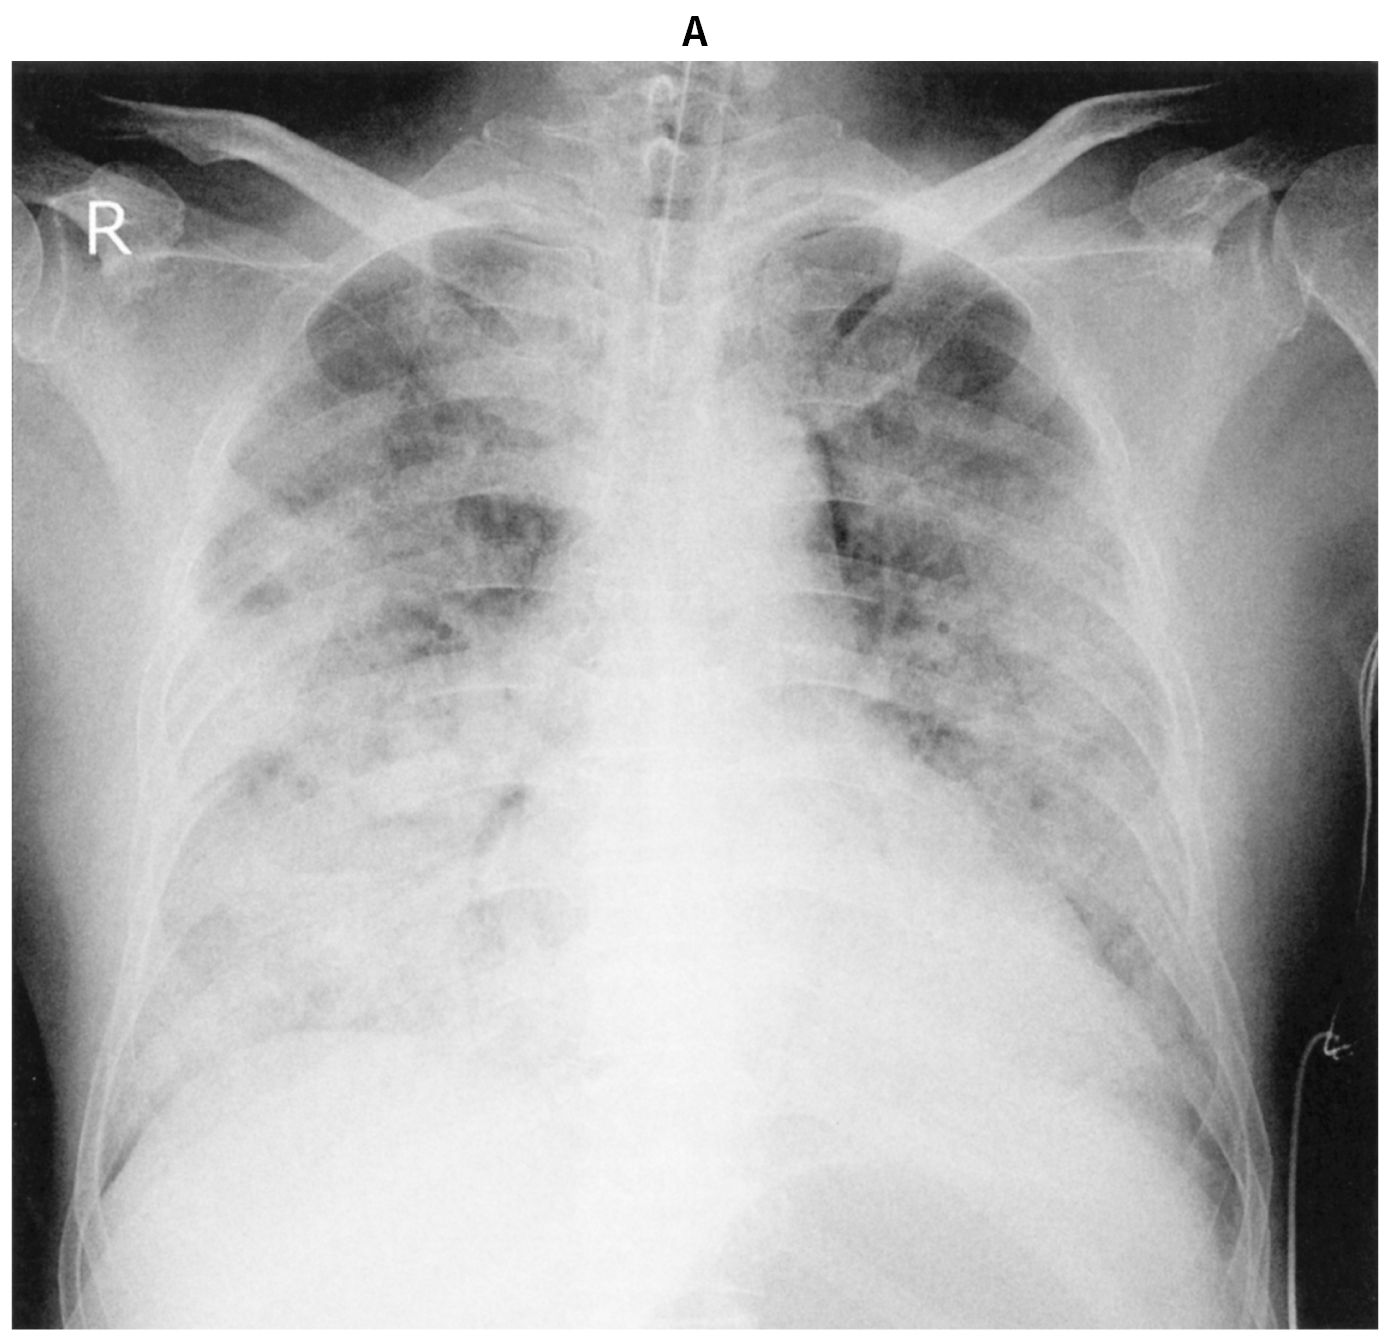

65歳の男性。呼吸困難と意識障害を主訴に救急搬入された。海でシュノーケリング中に溺れすぐに救助されたが,激しい咳嗽と呼吸困難を訴え,意識がもうろうとしており救急要請された。救助30分後の病院搬入時,顔色不良。意識レベルはGCS 8(E3V1M4)。体温37.1℃。脈拍128/分,整。血圧110/84 mmHg。呼吸数28/分。SpO2 84%(リザーバー付マスク10L/分 酸素投与下)。頸静脈の怒張はなく,両側肺でcoarse cracklesを聴取する。心音は整で頻脈,心雑音は聴取されず,下腿浮腫も認めない。血液所見:赤血球468万,Hb 12.2g/dL,Ht 37%,白血球7,100,血小板27万。血液生化学所見:総ビリルビン0.7mg/dL,AST 18U/L,ALT 14U/L,LD 250U/L(基準124~222),γ-GT 15U/L(基準13~64),CK 144U/L(基準59~248),尿素窒素18mg/dL,クレアチニン0.8mg/dL,血糖120mg/dL,Na 146mEq/L,K 3.6mEq/L,Cl 113mEq/L。CRP 0.1mg/dL。動脈血ガス分析(リザーバー付マスク10L/分 酸素投与下):pH 7.30,PaCO2 53 Torr,PaO2 50 Torr,HCO3 15mEq/L。心電図は洞性頻脈。ベッドサイドで行った心エコー検査では壁運動は正常で,心嚢液の貯留も認めない。救急室で気管挿管後,気管チューブから海水が吸引された。挿管後に撮影した胸部エックス線写真(A)と胸部単純CT(B)とを下に示す。

無料会員登録していただくと、実際の解説をすべて見ることができます。急性の呼吸困難を主訴とする疾患としては,喉頭浮腫,気道異物,自然気胸,気管支喘息,慢性閉塞性肺疾患の急性増悪などの呼吸器疾患,心不全(急性,慢性の急性増悪),肺血栓塞栓症などの循環器疾患が代表的である。この症例では呼吸器感染症と心不全が疑われるが,胸部エックス線写真は肺炎像というよりも両心不全を示唆する所見を示している。診断:心不全(両心不全)(Nohria分類wet and warm) 選択肢考察 ×a 強い呼吸困難,胸痛などにより安静が保てない場合には,血管拡張による前負荷軽減と,交感神経抑制による心筋酸素消費量の減少を目的としてモルヒネを使用する。この症例ではモルヒネが必要となるほどの興奮状態ではない。